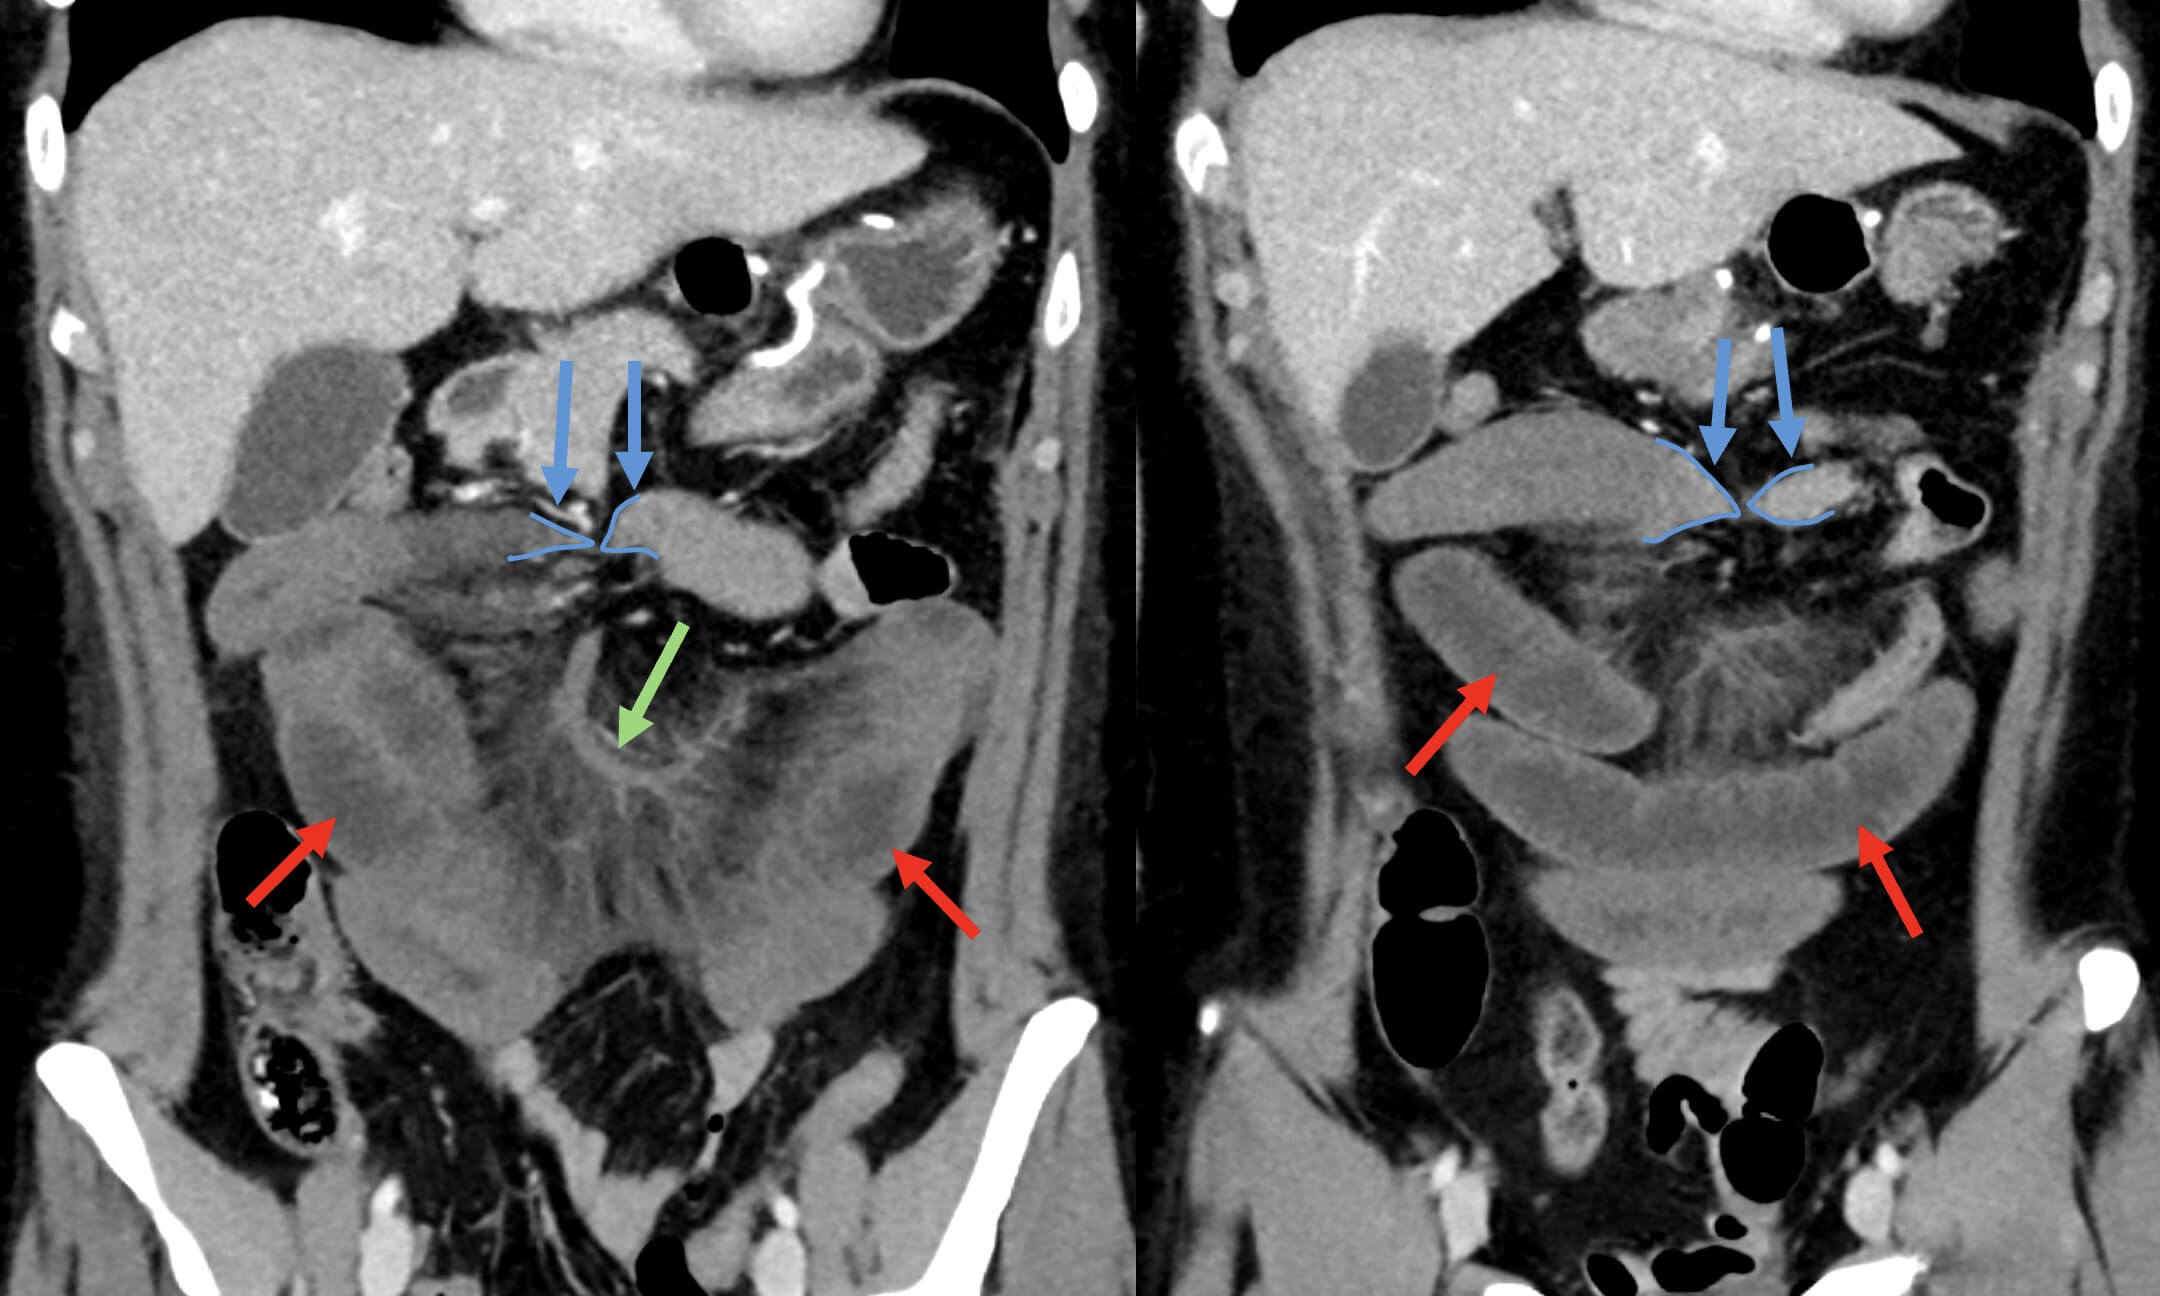

– Khi quai ruột có hai điểm tắc, vị trí chuyển tiếp có thể nằm xa nhau hoặc nằm sát nhau tạo thành một vòng khép kín => Do bị kẹt cả đầu vào và đầu ra, dòng máu đến và đi bị cản trở, dẫn đến nguy cơ thiếu máu ruột và hoại tử.

– Nguyên nhân thường gặp: do dính, xoắn ruột hoặc thoát vị nội. Nguy cơ nghẹt và nhồi máu ruột rất cao với tỷ lệ tử vong là 10-35%.

+ Quai ruột tới và vòng ruột xoắn giãn, quai ruột đi xẹp.

+ Quai ruột tới giãn, vòng ruột xoắn xẹp, quai ruột đi xẹp.

+ Quai ruột tới và quai đi đều xẹp, vòng ruột xoắn giãn.

+ Dạng chữ “U” hoặc chữ “C”: nếu quai ruột đóng cùng trên một mặt phẳng. Tái tạo theo nhiều mặt phẳng giúp phát hiện quai ruột đóng tốt hơn.5. Nguyên nhân

– Dấu hiệu xoáy nước “Whirlpool sign”: tại vị cuống xoắn, mạc treo và mạch mạc treo quấn hình xoáy trôn ốc.